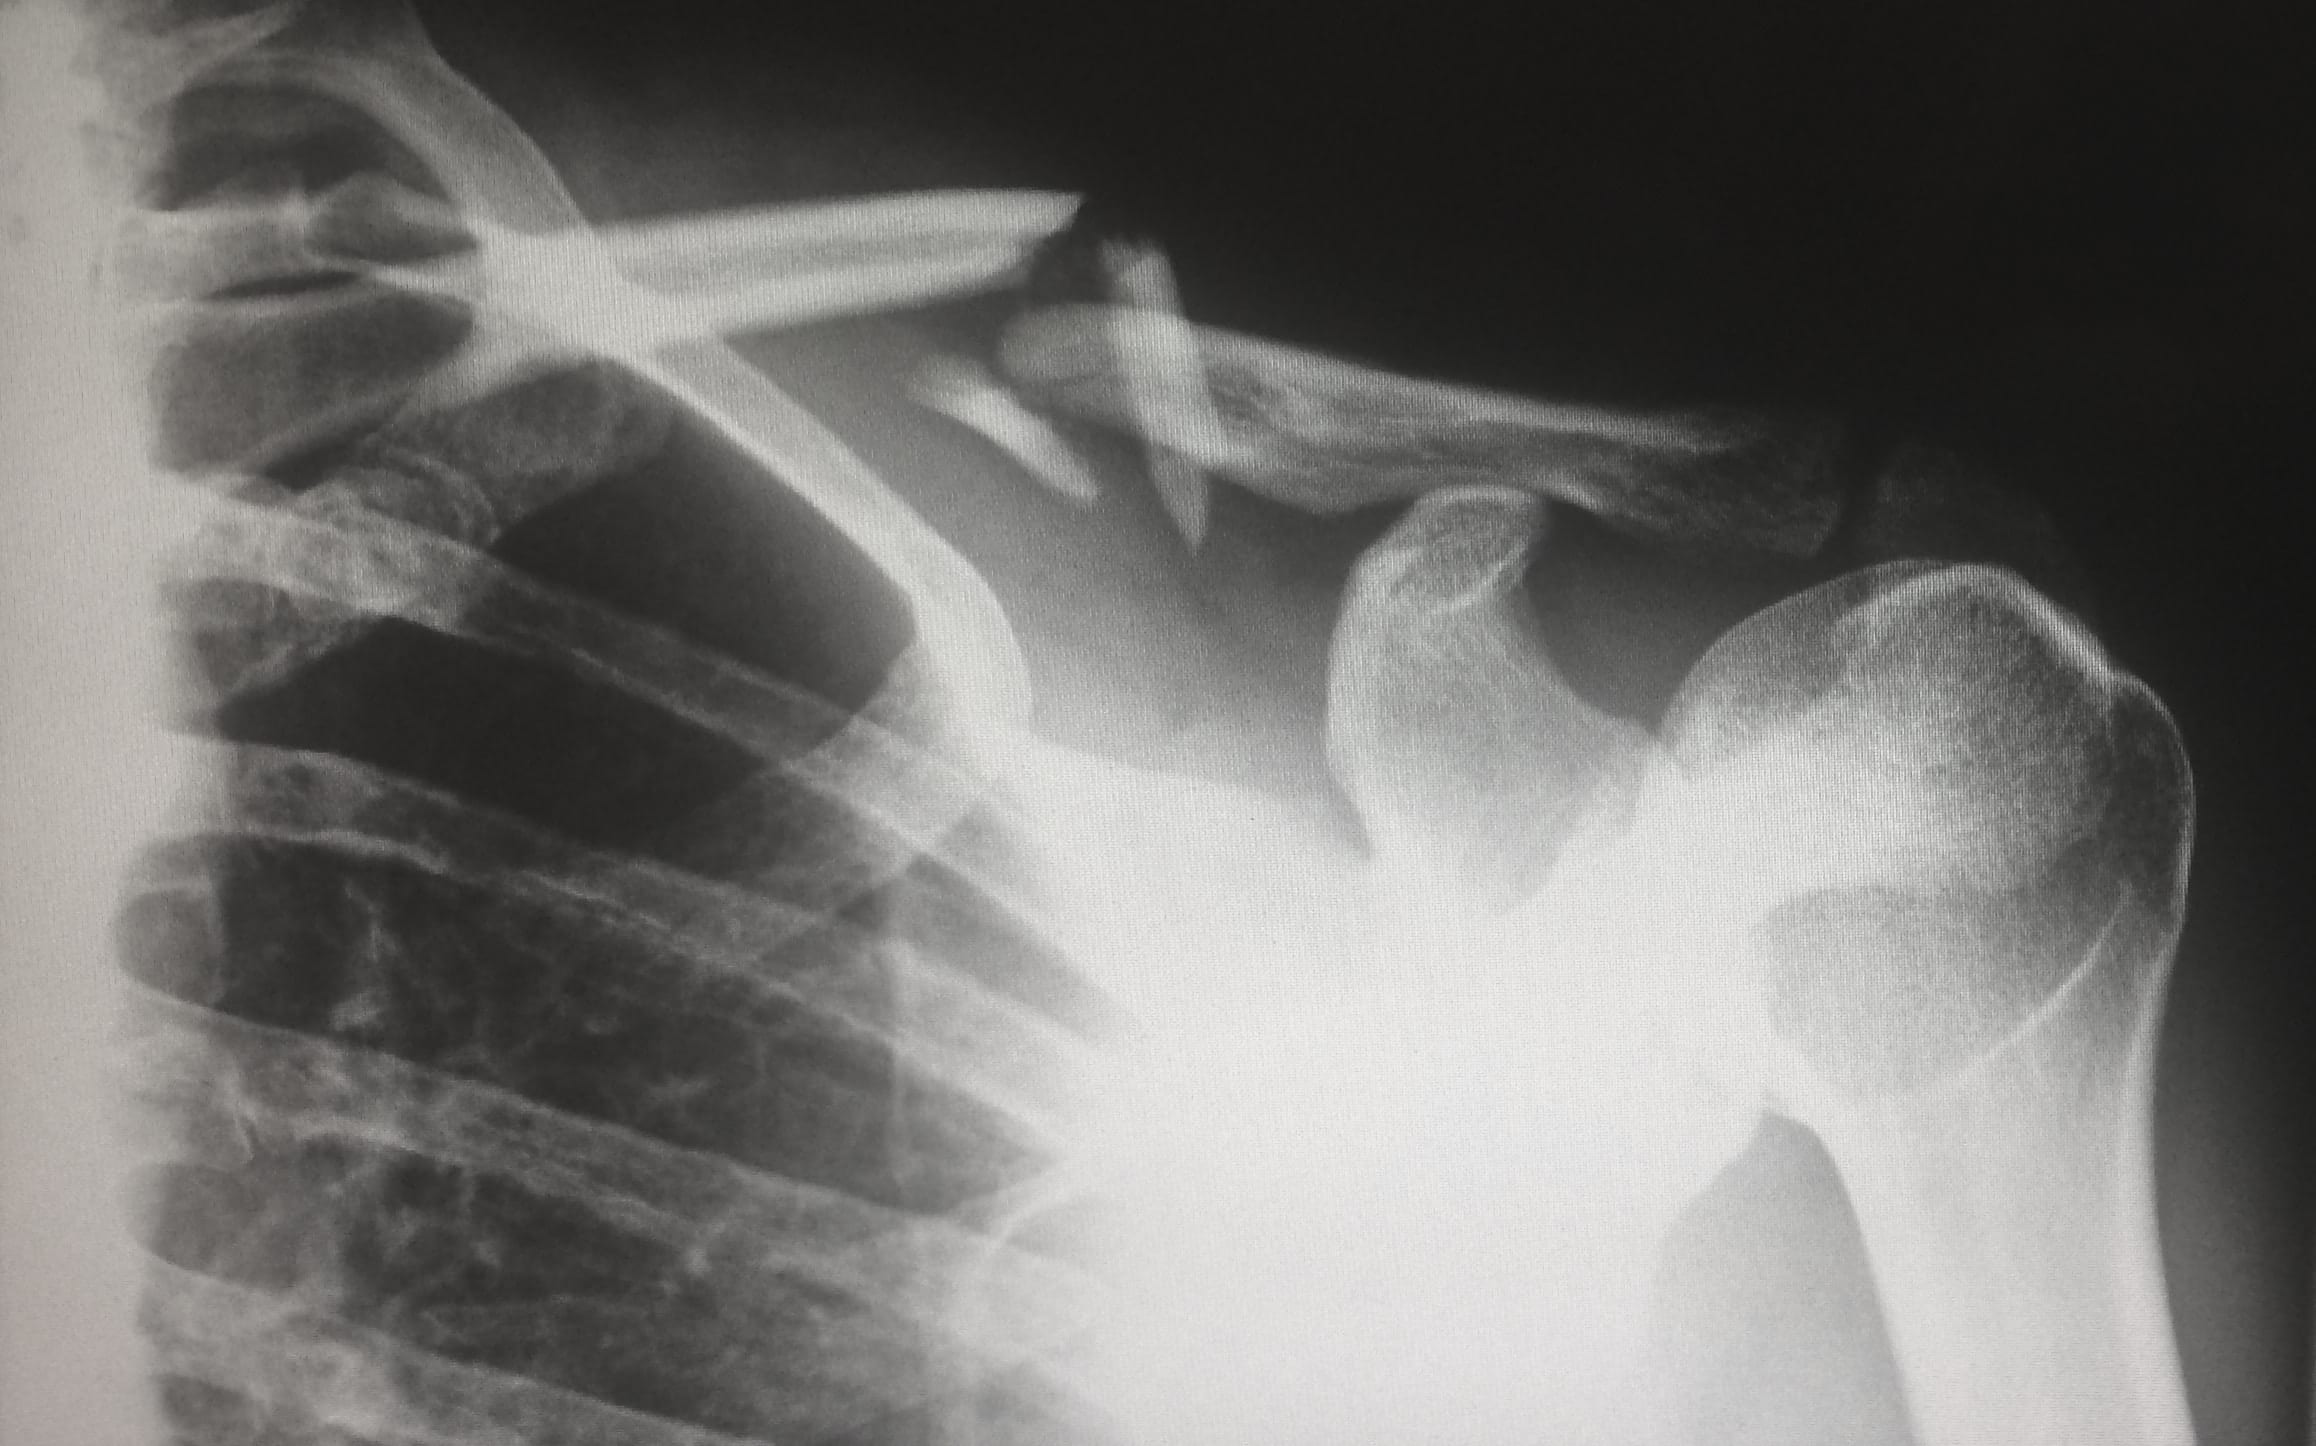

X-ray showing broken clavicle; image by Harlie Raethel, via unsplash.com.